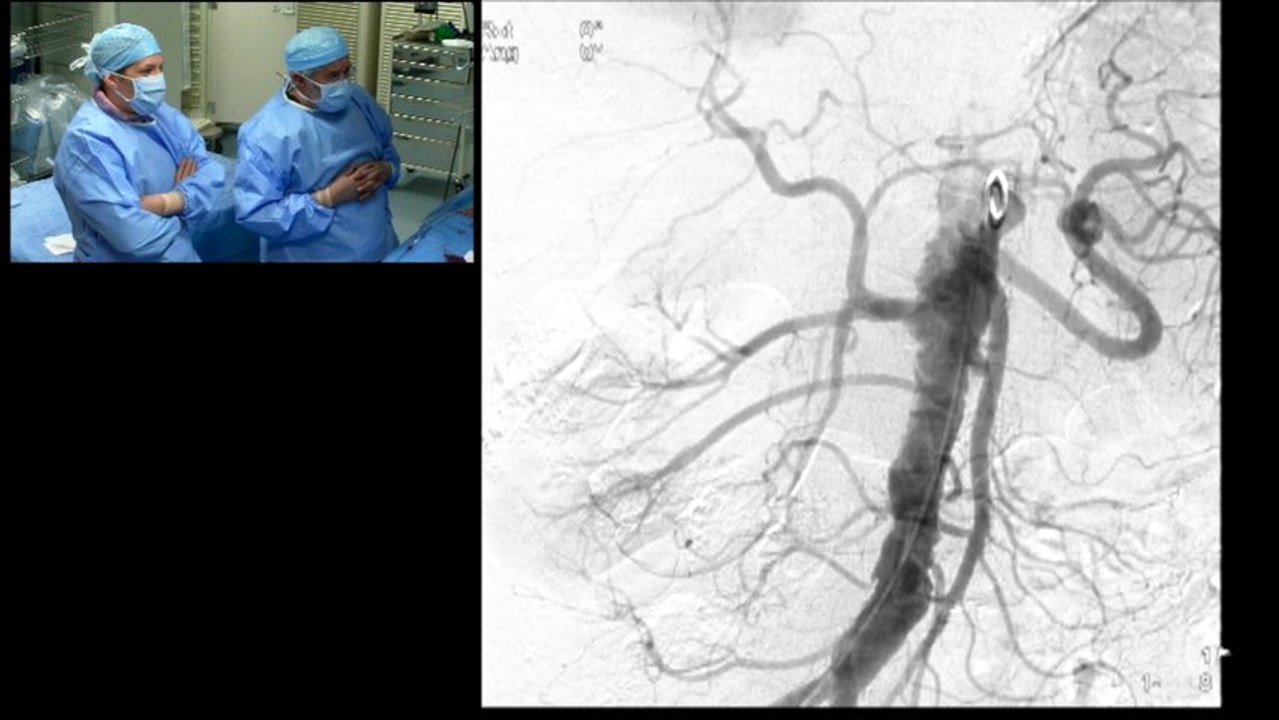

10 tibio-peroneal artery atherectomy (rotablator) antegrade approach incathlab.com